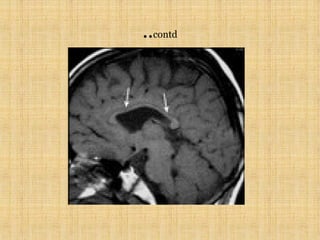

..CONTD

…CONTD

AXIAL T1 IMAGE SHOWING HYPERINTENSE

SIGNAL ALONG THE GYRUS SHOWING

CORTICAL LAMINAR NECROSIS

AXIAL T1 IMAGESHOWING HYPERINTENSE SIGNAL ALONG THE GYRUS SHOWING CORTICAL LAMINAR NECROSIS